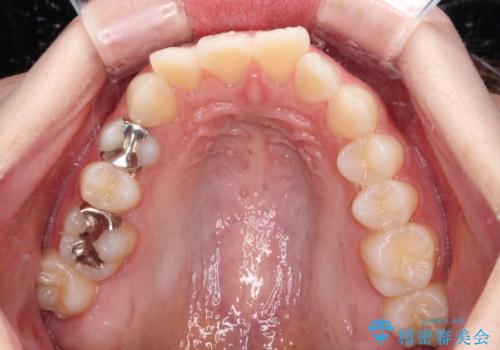

- 上の前歯が下唇に当たる感覚と奥歯の欠損を気にして来院された患者様です。

上顎前歯の突出感は、上顎全体が前方に位置していることが原因であったため、補助装置により上顎全体を後方に移動させることとしました。

後方移動と同時上下歯列をワイヤー装置にて整え、奥歯の欠損部には矯正治療の途中でインプランを埋入していくこととしました。